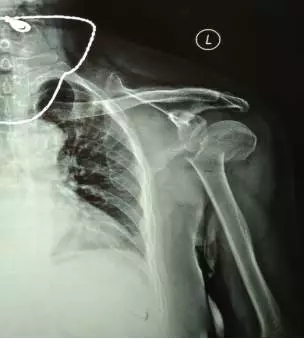

70多歲的鮑阿婆在家人陪同下來到上海大團醫(yī)院就診。大團醫(yī)院的醫(yī)生給鮑阿婆左肩部做了X線片檢查。片子拍出來竟然是左肱骨近端粉碎性骨折。外科頸,大結(jié)節(jié)都碎了,而且骨折端移位很嚴重。

正骨科的虞杰主任、邵鵬及葉華磊醫(yī)生看到鮑阿婆的片子也是一皺眉頭,這么厲害的骨折,還真是少見,而且移位這么嚴重,手法復(fù)位的難度也是相當(dāng)大的。不過患者的信任給了他們很大的動力,即使困難也要盡力幫患者。

整復(fù)前